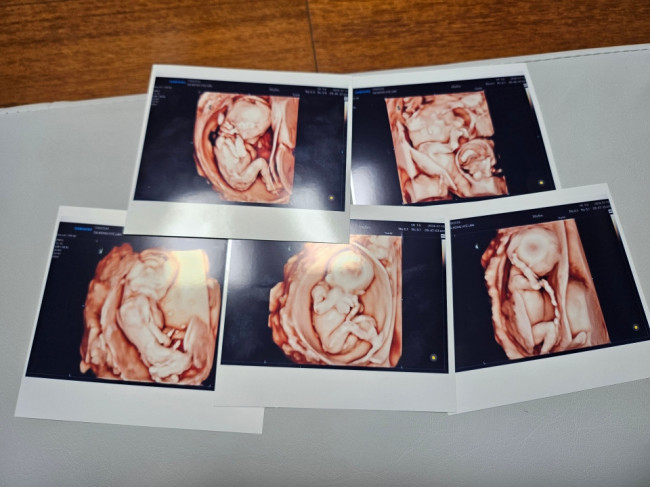

다섯쌍둥이 출산다섯쌍둥이 출산 (뉴스저널 코리아) 서울성모병원은 20일 낮 남자아이 3명과 여자아이 2명의 '오둥이'가 건강하게 태어났다고 밝혔다. 사진은 오둥이의 초음파 사진. 2024.9.20 [사진제공 서울성모병원]

20일 서울성모병원에 따르면 이 병원에서는 이날 낮 남자아이 3명과 여자아이 2명의 '오둥이'가 건강하게 태어났다.

더구나 이날 태어난 다섯명의 아기들은 자연임신으로 생겼다. 국내에서 다섯쌍둥이가 자연임신으로 생겨 건강하게 태어난 것은 이번이 처음이다.